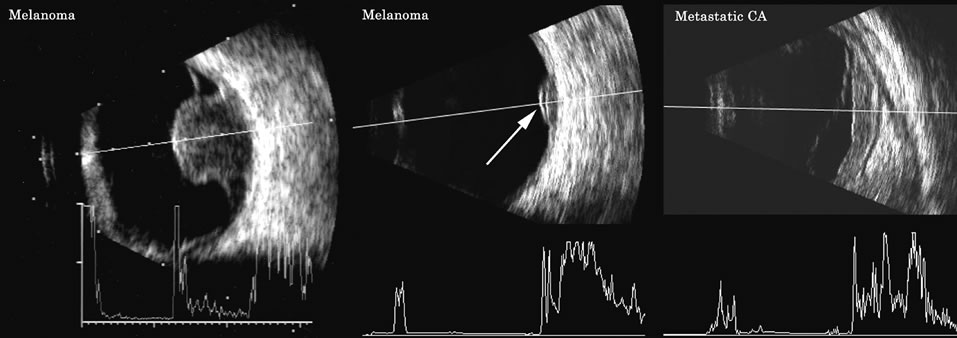

Malignant melanoma varies in its ultrasound presentation from a relatively homogeneous to heterogenous lesion on B-scan. The typical uveal melanoma absorbs sound so that the posterior section is relatively less echoic than the anterior aspect, producing a gradually decreasing amplitude, often to baseline on the A-scan (Fig. 21).

Melanomas also have varying amounts of melanin, a highly acoustically reflective pigment. As noted, melanomas characteristically show high reflectivity anteriorly, with decreasing reflectance as the sound traverses the tissue. This produces the decreasing amplitude posteriorly in the tumor seen on A-scan and gray-scale B-scan. This effect often enhances the anterior scleral boundary. The posterior tumor border is thus measured as the first “rising” echo from the tumor decline, and it is most easily seen and accurately identified on B-scan.27

Metastatic carcinoma is more heterogeneous, producing a more uniform A-scan amplitude of roughly 50% to 80% of the “scleral” echo amplitude (see below) behind the tumor (Fig. 22). Hemangioma is a very highly reflective tumor with high amplitude all the way through the tumor of 80% to 100% of scleral echo amplitude (Fig. 23).

Fig. 22. Some hemangiomas and metastatic carcinomas may simulate a melanoma. They are differentiated on the basis of a very high amplitude internal echo complex for the hemangioma, a moderately low but sustained echo pattern for the metastasis, and an A-scan with decreasing reflectance as the tumor thickness is traversed. In the center scan of a melanoma, note the double anterior layer caused by edema fluid underlying the crest of the melanoma (arrow).

The differentiation of tumor tissues is made possible by differences in cellular organization and concentration.29 Acoustically, these are termed as differences in backscattering properties.30–32 A homogeneous solid tissue, such as the lens or the optic nerve, may present few or no echogenic discontinuities and thus appear anechoic and cyst-like. (An echogenic discontinuity is technically an acoustic impedance mismatch in which the acoustic impedance is the product of the density and the speed of sound in each tissue.) A fluid–smooth tissue boundary has a high mismatch or discontinuity and thus produces a high-amplitude echo. A hemangioma with alternating blood- and tissue-lined sacs thus produces a solid-appearing tissue with high-amplitude echoes seen at all depths of the tissue. A metastatic tumor is nearly always a very heterogeneous tissue with randomly organized clumps of similar cells bounded by strands of vessels, necrotic areas, and connective tissue, thus producing a pattern of moderately high-amplitude sustained echoes.